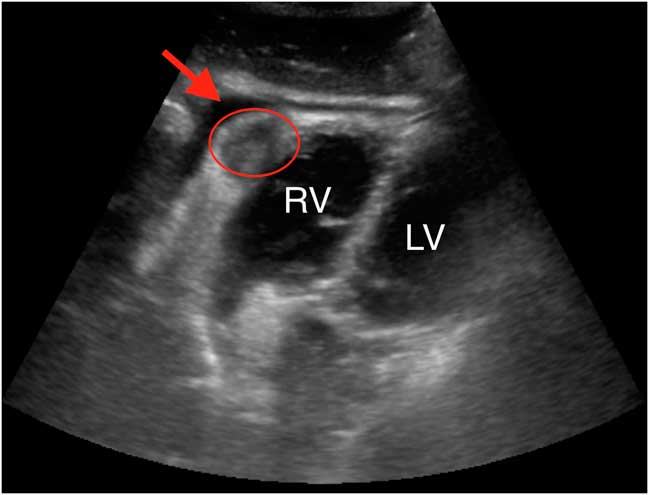

A 51-year-old female with esophageal cancer presented with a 1-day history of retrosternal chest pain with hypotension. She had no previous cardiac disease but was a chronic smoker. Her electrocardiogram (ECG) revealed inferior ST elevation. Given her well-looking appearance and active malignancy, etiologies other than ST elevation myocardial infarction (STEMI) were considered. Point-of-care ultrasound (POCUS) was performed to evaluate for a pericardial effusion (PCE). It revealed a small PCE and a mass in the inferior wall of the right ventricle (RV) (Figure 1).

Figure 1 Subxiphoid cardiac view revealing a cardiac mass (red oval) in the inferior wall of the right ventricle (RV), adjacent to the left ventricle (LV), and a small pericardial effusion (red arrow).

Additional cardiac ultrasound views demonstrated appropriate fractional shortening and no regional wall motion abnormalities. Troponin levels were elevated but stable. Cardiology reviewed the case and POCUS images and agreed that a STEMI was unlikely. Therefore, the cath lab was not activated. Pulmonary embolus investigations were negative. Cardiac magnetic resonance imaging confirmed a mass in the RV wall believed to be metastatic esophageal cancer and the cause of her symptoms.